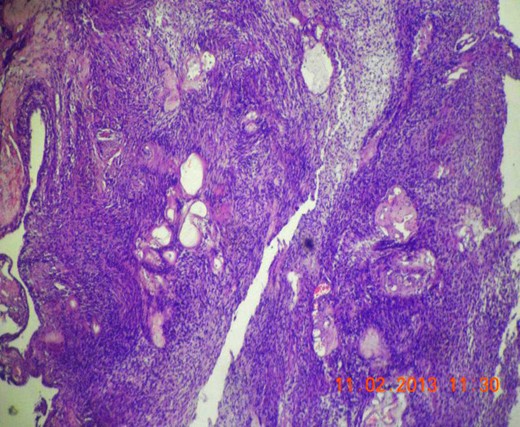

Gross appearance showed 6 × 4 × 4 cm smooth encapsulated right thyroid swelling with a posterior cystic area which was yellowish brown in colour. Walls of the cyst were bright yellow with polypoid areas (Fig. 4). Histology showed classical Antoni A (hypercellular areas) with Verocay bodies and Antoni B (hypocellular) pattern, with interspersed thyroid cells along the periphery (Figs 5–7). The lesion was reported to be arising from within the thyroid gland itself and not extrinsic to it.

Microscopic section (H&E slide, 40×) of well-encapsulated lesion with hyper- (Antoni A) and hypocellular (Antoni B) areas. Multiple cystic areas are also seen.

Microscopic section (H&E slide, 40×) of Verocay bodies within Antoni A pattern.

Microscopic section (H&E slide, 100×) of magnified view of a region in Fig. 6 showing Verocay bodies.

Pre-operative CT scan was done in three cases [4–6]. The lesion was homogeneous and of low density on plain CT, with good post-contrast enhancement. Sujita et al. [6] explained that the well-enhancing areas on CT corresponded to the hypercellular Antoni A areas, whereas those showing poor enhancement corresponded to Antoni B pattern.